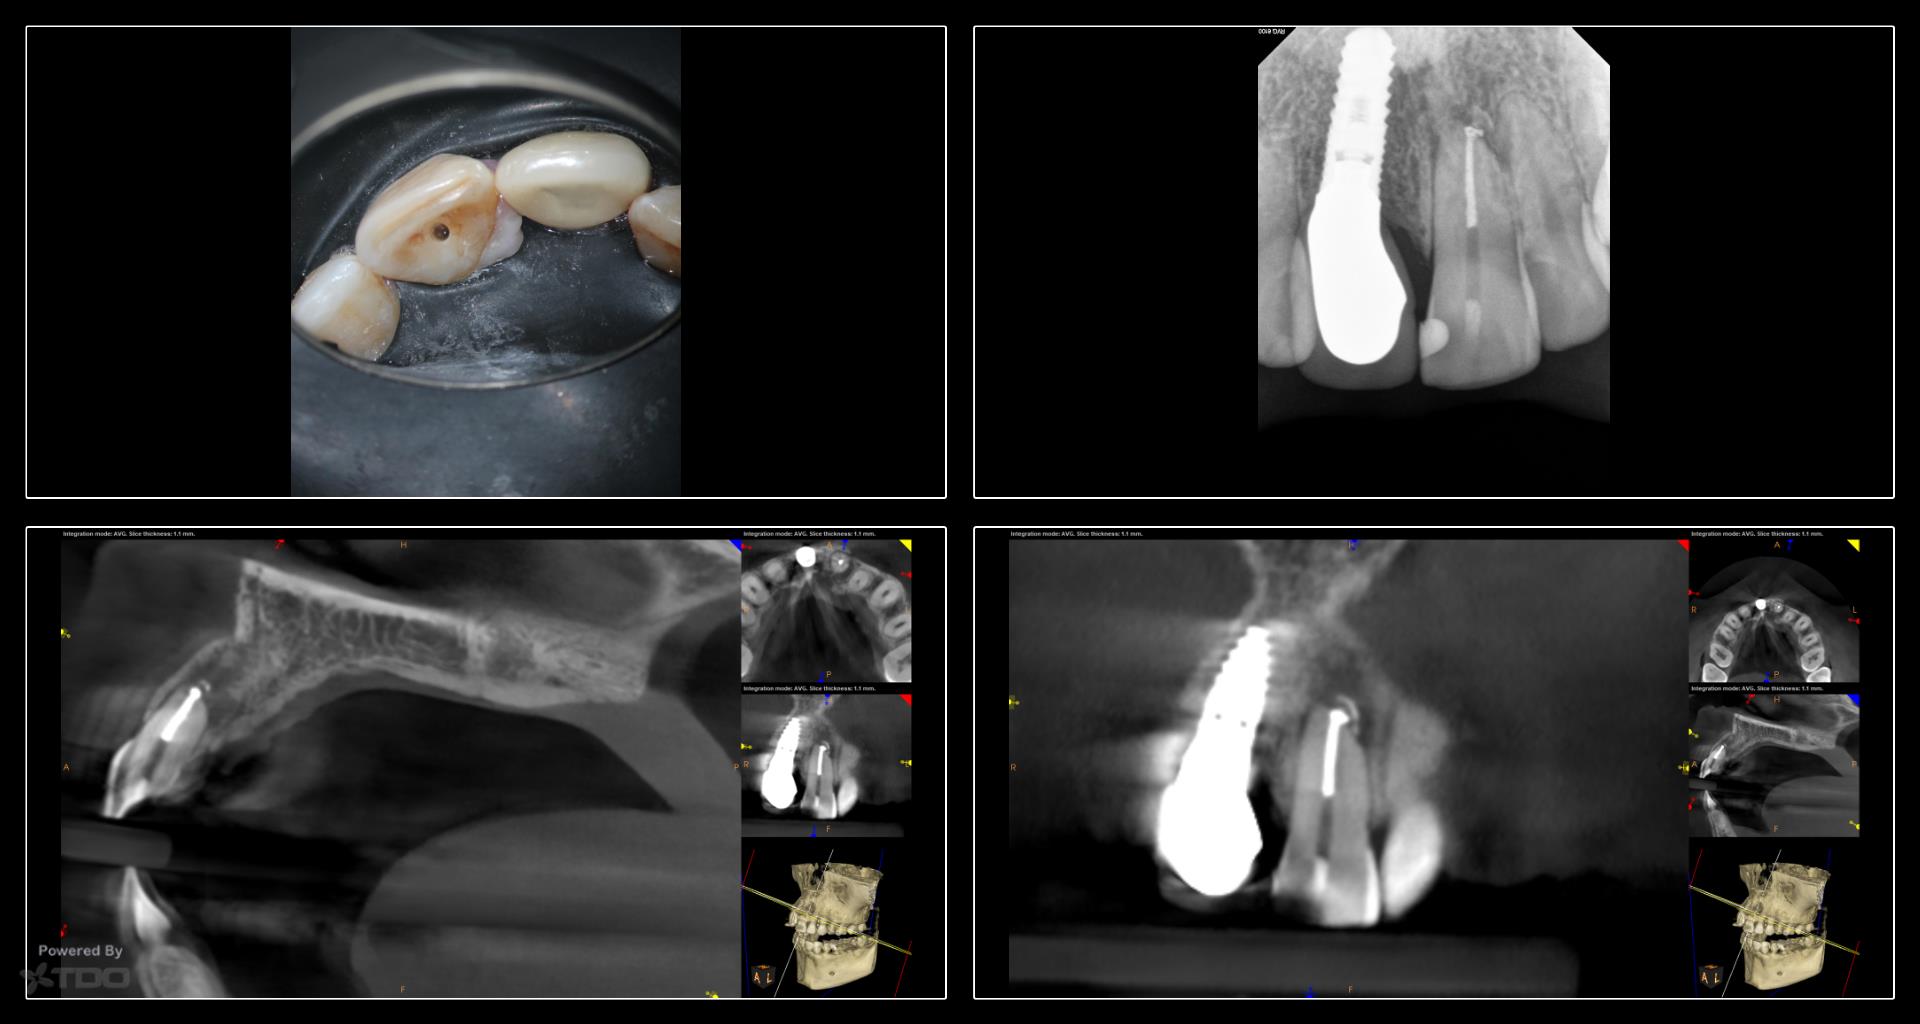

Collage-232629-Page00

This case was started in February and completed on Monday. We are currently bleaching the tooth. The buccal plate has regenerated rather nicely and the finding is continuing to heal. -Charles